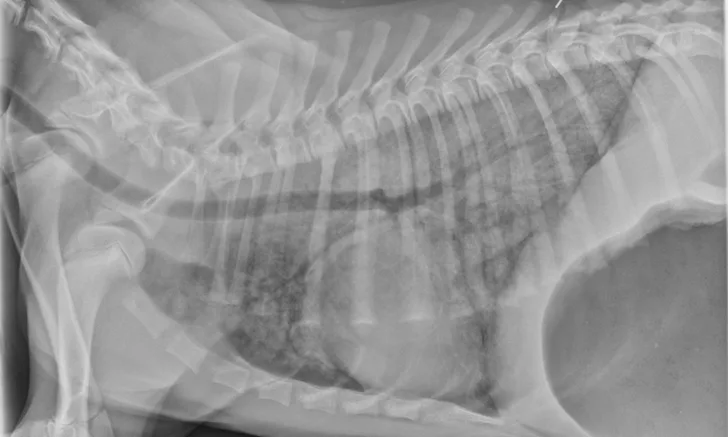

Thoracic radiographs can appear normal initially, but changes to the pulmonary parenchyma may become more apparent within 24 to 72 hours as respiratory injury progresses. Evidence of patchy pulmonary edema with bronchial, interstitial, or alveolar patterns may be observed [Figures 1 and 2].6,13,16,19 Right middle lung lobe consolidation and pleural effusion in cats have been reported.6,13,16 An alveolar pattern may be seen on serial radiographs in patients that develop secondary bacterial pneumonia.6

Lateral thoracic x-ray of a dog showing diffuse opacity of lung parenchyma.

FIGURE 1

A severe, diffuse patchy interstitial-to-alveolar pattern, more severe in the mid-to-caudodorsal lung fields, in a dog with smoke inhalation injury after a house fire